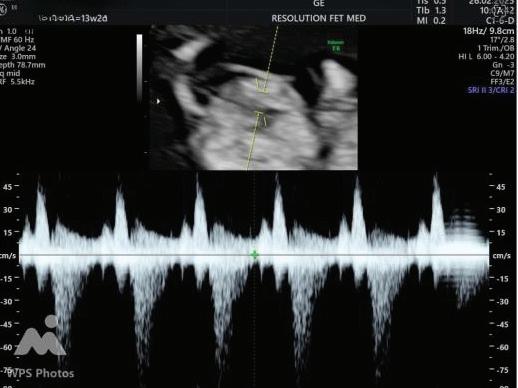

2. NUCHAL TRANSLUCENCY (NT) SCAN

• This is the cornerstone of first trimester screening.

1. NT is the sonographic appearance of subcutaneous accumulation of fluid behind the fetal neck, below the skin in the first trimester of pregnancy.

2. Measured in mid-saggital section only.

3. Measured between 11-14 weeks.

4. CRL between 45-84mm.

5. Magnified to include only head and upper thorax.

6. Fetus should be in neutral position.

7. Demostrate fetus separate from amnion.

8. Measurement should be ON to ON (cross bar of the callipers should be such that it’s hardly visible and merges with white line, not nuchal fluid).

During the scan more than one measurement should be taken and maximum value should be considered.